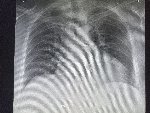

Здравствуй двачик, пишет вам простой рентгенолог из мухосранской поликлиники, сегодня я буду флексить зарплатой за ноябрь! Аж ПЯТЬДЕСЯТ ТРИ ТЫЩИ ПЕРЕВЕДУТ! С пруфом! А чего достигли вы? Ну и в доктора тож поиграем! Я буду вам картинки показывать, а вы пиздецомы находить! Найдите пиздецому на фтчк! Отчет еще по фог считать квартальный и годовой сегодня :-(